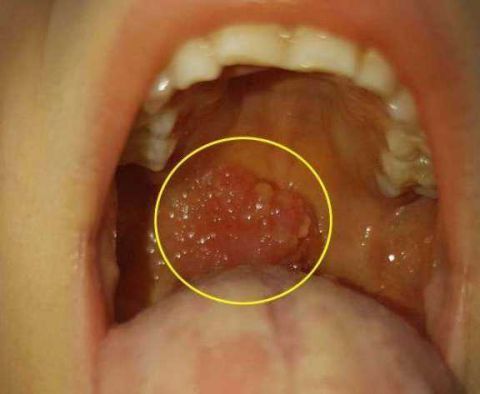

扁桃体大面积起泡,伴随高烧(高达39.

图片尺寸480x640